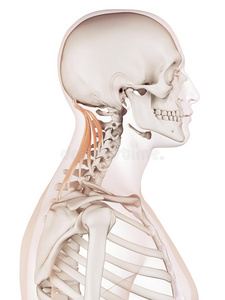

人的劲背后面是不是有两个凸起的骨头.就是劲行和后背那里.

图片尺寸620x465

脖子后面骨头凸起图片

图片尺寸225x300